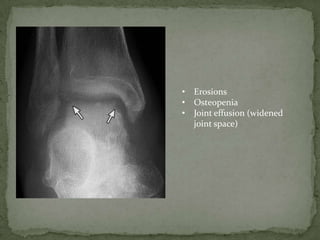

ANKLE -

• Erosions

• Osteopenia

• Joint effusion (widened

joint space)